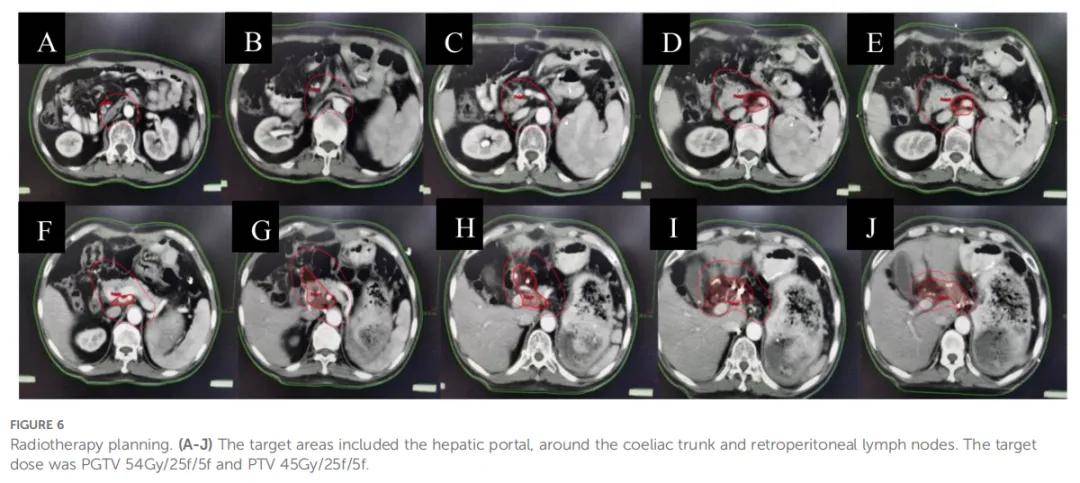

术后患者出现胃排空延迟(残胃潴留)及乏力症状。经科室讨论后,将治疗方案调整为 4 个周期XELOX方案化疗(奥沙利铂 125 mg 第 1 天给药+卡培他滨 1.5g 每日 2 次,第 1-10 天给药,每 2 周为 1 周期),联合纳武利尤单抗免疫治疗(300 mg 静脉输注,每 3 周 1 次)。7 月 15 日再分期CT未见复发或转移征象,提示治疗持续缓解(部分缓解,PR)。随后于 2021 年 8 月 4 日至 9 月 7 日对高危淋巴结区域(肝门区、腹腔干周围、腹膜后)实施巩固放疗(图6),同步给予卡培他滨(放疗日按 825 mg/m²剂量每日 2 次给药)及纳武利尤单抗治疗。放疗处方剂量为:受累淋巴结计划大体肿瘤靶区(PGTV)54 Gy,分 25 次照射;淋巴结预防照射计划靶区(PTV)45 Gy,分 25 次照射(二者单次分割剂量分别为 2.16 Gy、1.8 Gy,每周照射 5 次)。患者对治疗耐受良好,仅出现I级胃肠道不良反应。

▲图6 放疗计划